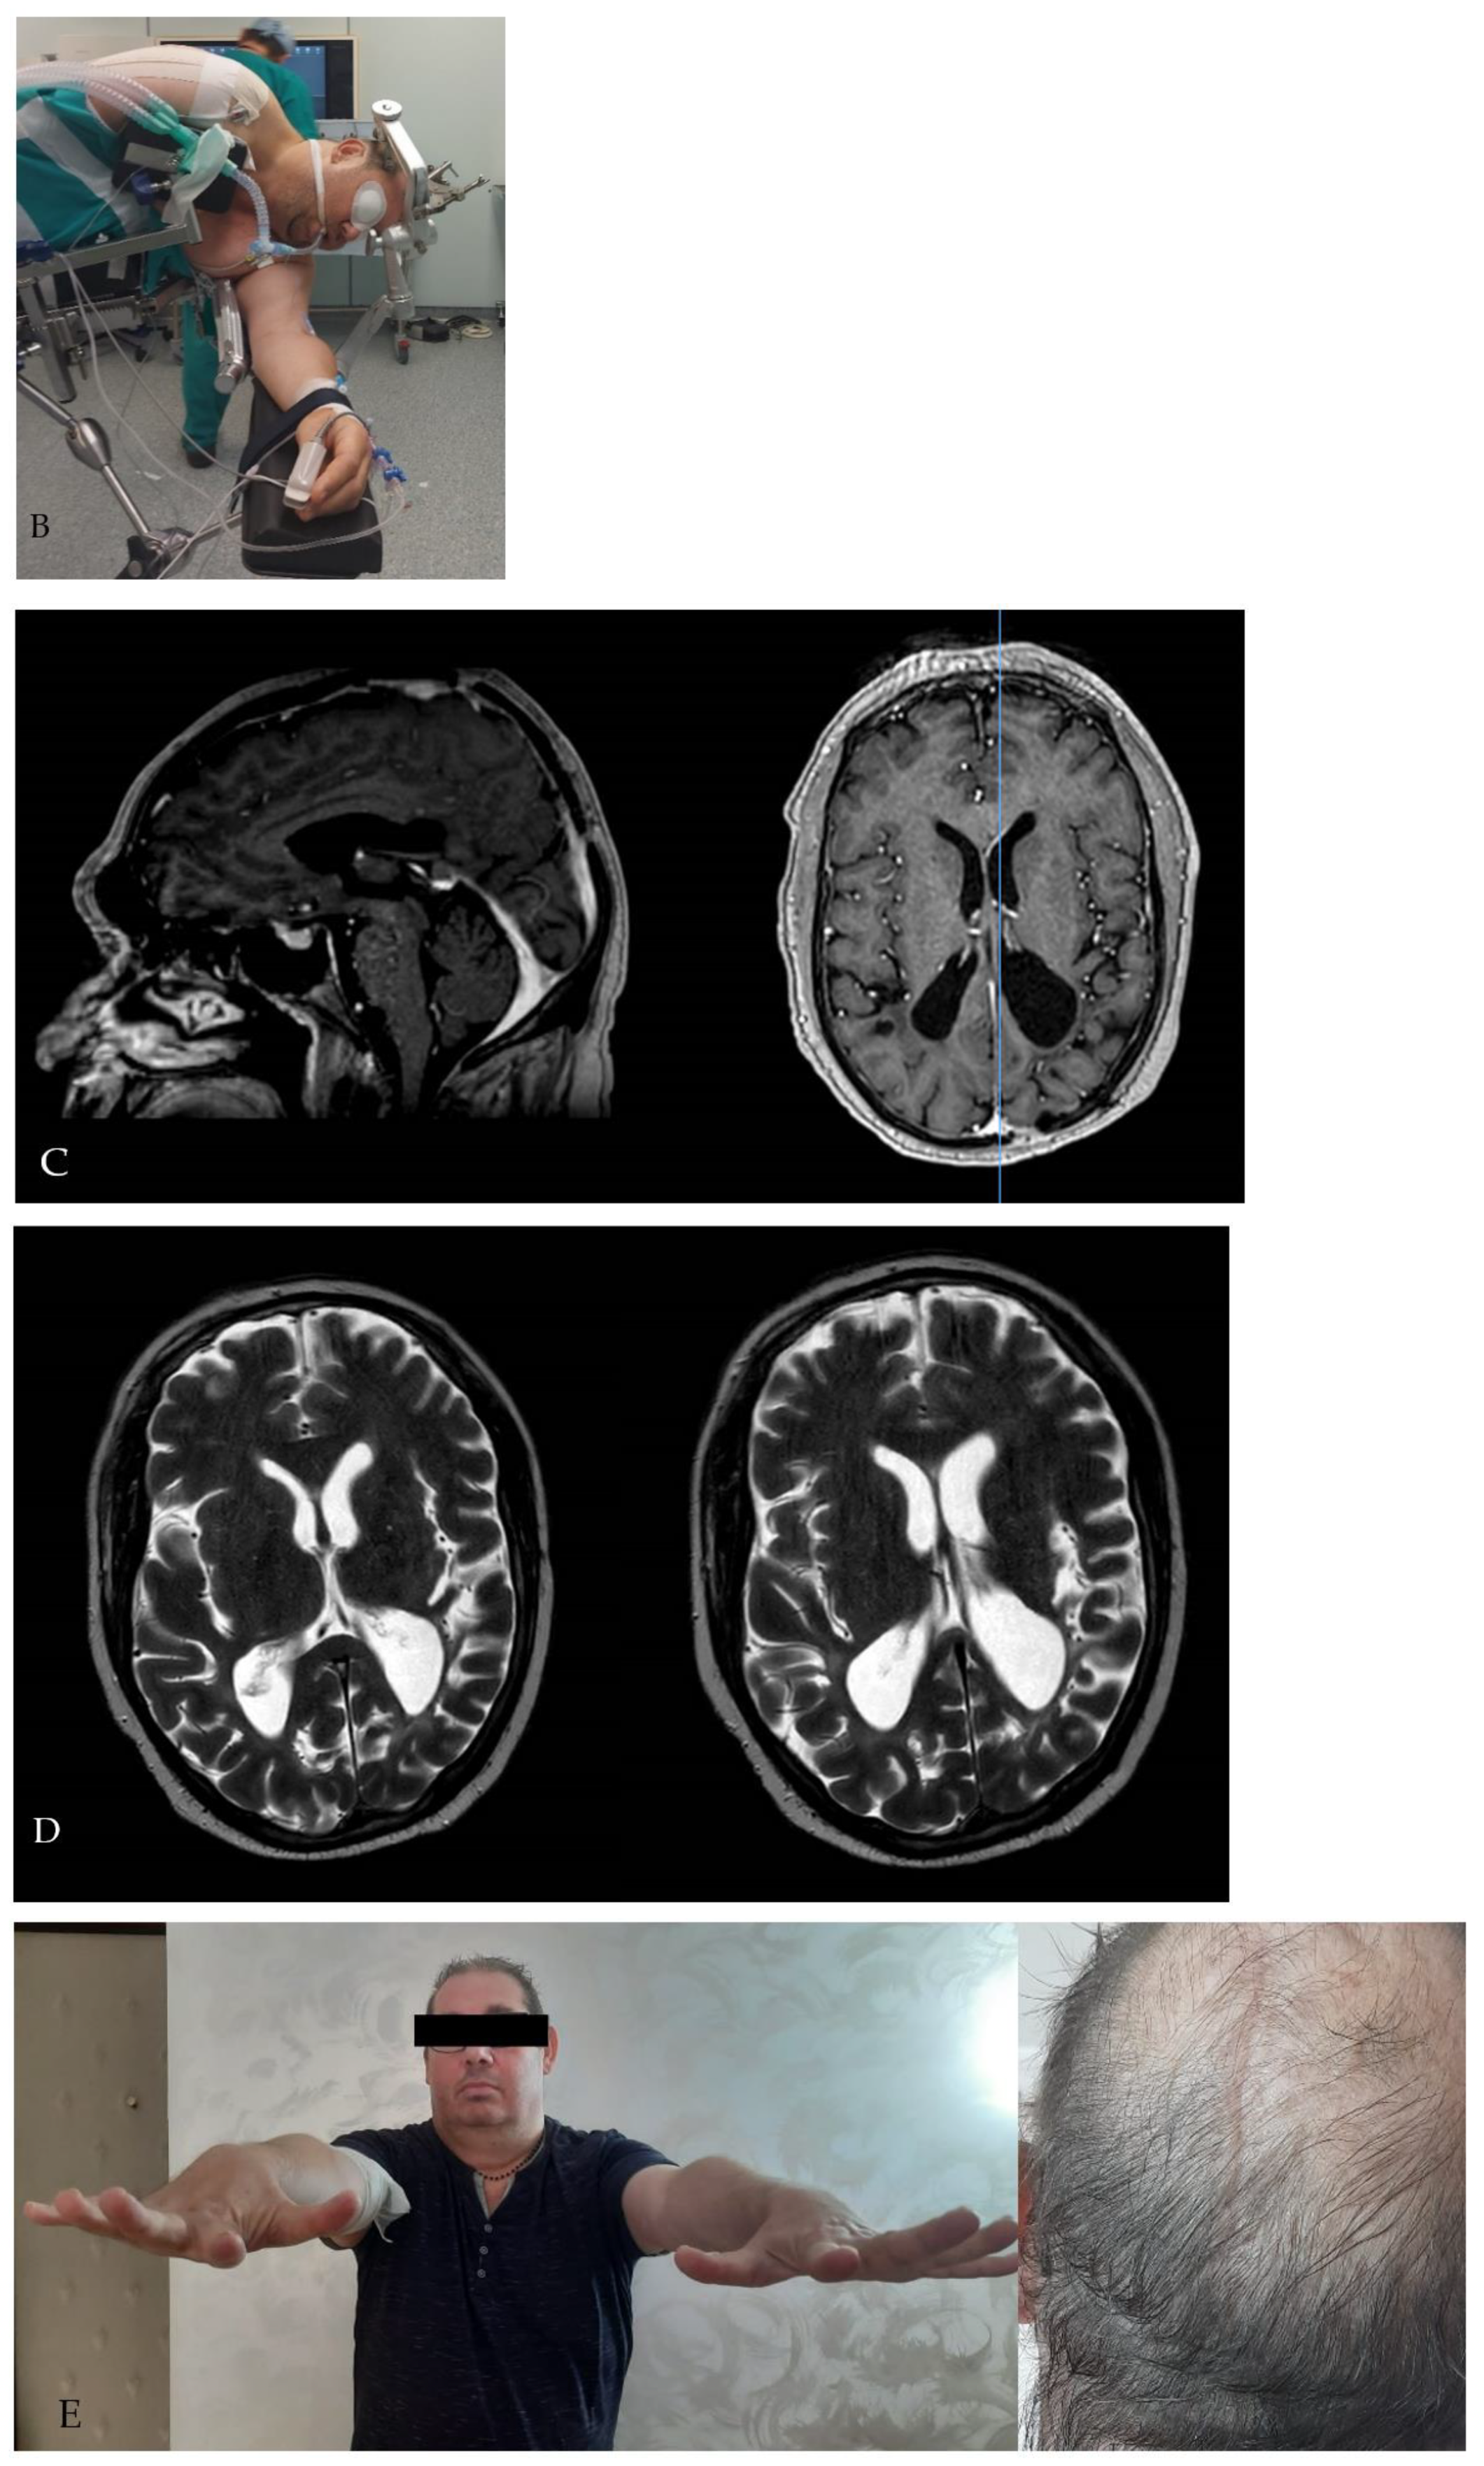

Figure 2. Patients were positioned in the three-quarter prone position with the head in the dependent oblique posture. The purpose of this maneuver is to obtain an enlargement of the interhemispheric window by inducing the cerebral hemisphere to fall away from the falx due to the effect of gravity. In this way, the need for cerebral retraction is significantly reduced, whereas the possibility to increase the angle of the “medial to lateral” dissection is augmented.

All patients underwent general anesthesia. All the procedures were performed by the senior author (PC). Before final positioning, a lumbar drain was placed to ensure adequate brain relaxation in all patients. Patients were placed in the standard three-quarter prone position with their head fixed in a 3-pin Mayfield head clamp in order to place the ipsilateral mastoid surface at the highest point of the surgical field. This can be obtained by combining the flexion of the head with a 15–20 degree rotation contralateral to the lesion and a latero-flexion towards the opposite side (Figure 2). The purpose of this maneuver is to obtain an enlargement of the interhemispheric window by inducing the cerebral hemisphere to fall away from the falx due to the effect of gravity. In this way, the need for cerebral retraction is significantly reduced, whereas the possibility to increase the angle of the “medial to lateral” dissection is augmented. Since June 2010, the Neuronavigation system (Stealth-Station AxiEM, Medtronic) and intraoperative monitoring of motor- and somatosensory-evoked potentials were systematically used. A linear or horseshoe parieto-occipital incision is performed. The incision should expose the sagittal as well as the lambdoid suture. Mannitol was administered at this time.

Our experience with IITA prompts us to state that in this approach, the key to increasing the angle exposure of the lateral wall of the atrium is the correct head positioning. In fact, the three-quarter prone position with the head in the dependent oblique posture toward the side of the lesion enlarges the interhemispheric space by inducing the cerebellum to fall way from the falx due to the effect of gravity. This aspect, coupled with the deliquoration induced by the interhemispheric dissection, limits the need for brain retraction and increases the angle of surgical exposure facilitating the visualization of the lateral wall of the atrium. Moreover, this position places the axis of the lesion in a nearly perpendicular plane with respect to the working angle, increasing the operative comfort for the surgeon.

Surgical treatment of tumors of the atrium is challenging because of the need to conjugate a total removal of the lesion with respect to the anatomo-functional integrity of the white matter fibers encircling its walls. The IITA was successfully used in seven patients, permitting us to obtain a total removal of the lesion in all the cases treated without experiencing postoperative neurologic deficits related to white matter fiber injuries. The key to the successful execution of this approach is the correct positioning of the patient. The dependent oblique posture in the three-quarter prone position facilitates the enlargement of the interhemispheric fissure, increasing the working angle and facilitating the exposure of the lateral wall of the atrium.